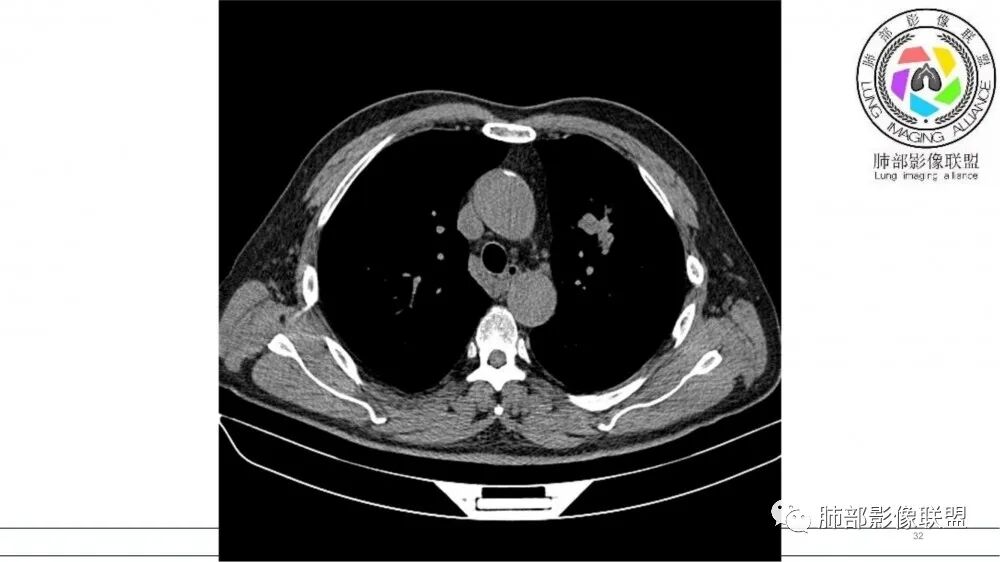

左肺上叶前段支气管内铸形生长软组织影,增强后均匀强化,远侧见斑片状磨玻璃影。考虑恶性病变,粘表?粘液腺?

老年男性,左肺上叶前段支气管内铸形阴影,增强后病灶不均匀强化,内部有坏死?远端可见斑片状阴影(阻塞性肺炎)。考虑恶性病变,老年人,鳞?类癌?粘表不能排除。

左肺上叶前段支气管杵状指样扩张,内见实性组织阻塞性,并强化明显,边缘饱满,周边多发小斑点影,小花小草征,老年男性,长期吸烟史,方向恶性,首选支气管内浸润鳞Ca可能性大。

男,70岁,吸烟史,咳嗽,胸闷憋气一个月,左肺上叶不规则形软组织密度影,病灶沿支气管走形,周围见粟粒及棉絮样稍高密度影,增强扫描病灶内见少许坏死,考虑鳞癌可能,鉴别结核。

老年男性,肺气肿,吸烟史,左肺上支气管腔内铸型高密度影,呈指套状,远端多发树芽,增强不均匀强化,考虑鳞癌,鉴别小细胞癌

B3指套征,常规不是鳞癌就是ABPA,有强化丶血管造影征,倾向于鳞癌

病灶沿支气管生长,强化不均匀,坏死不明显,血管自然进入,支持恶性,小在先,鉴别淋巴瘤

老年男性,吸烟史,左肺上叶支气管塑形生长肿块,整体边缘较圆钝,不均匀强化,血管走形,形态较纤细,病灶远端可见花草样改变,恶性,先考虑小细胞癌鉴别鳞癌

老年男性,长期吸烟史。左上肺前段沿支气管走形的指套样病变,增强可见病灶强化(排除结核、ABPA(也无气喘症状)),远端多发点状高密度影。考虑恶性肿瘤,鳞癌可能性大。

指套征,扩张支气管内软组织强化,远侧肺野阻塞性炎,纵隔、左肺门肿大淋巴结;老年男性,吸烟,考虑鳞癌,鉴别小

老年男性,术前检查肺气肿背景,左肺上叶结节,沿支气管蠕虫样生长,左肺门及纵隔淋巴结肿大,增强扫描不均匀强化,血管包绕,结合吸烟史,考虑小细胞肺癌。

老年吸烟男性,尖前段支气管内塑形生长,增粗蠕虫样,没有肺不张(排除鳞癌?),远端少许阻塞肺炎,增强低强化,锁定小

老年男性,吸烟,指套征,蠕虫征,阻塞性炎症不严重。可见血管穿行,密度均匀,轻度强化,首先考虑小细胞肺癌。鉴别鳞

2021年8月6日晨读病例结果:小细胞肺癌

指套征:是影像征象,胸部平片表现为手指状密度增高影,以肺门为中心呈放射状分布,CT显示扩张支气管内低密度黏液栓形成或实性病变,呈管状、树枝状或卵圆形密度增高影;支气管扩张伴近端梗阻时,扩张支气管内部黏液分泌物不能排出而形成。可以伴随远端空气潴留征、阻塞性炎症。

研究报道,中心型 SCLC 经 CT 扫描后通常支气管表现为鼠尾样狭窄,肺门或纵隔肿块明显,由于肿块沿管壁生长表现为顺延支气管形态的不规则形状。病灶相对特征性影像学表现比如鸭蹼状、腊肠状、葫芦状及葡萄状改变,可以出现血管包埋,很少有空洞、空泡,较少引发肺不张,阻塞性炎症成都较轻。与一般肺癌比较,恶性程度高,侵袭力强、病灶很小就容易远处转移!Herzberg 等[19]研究指出,20%以上 SCLC 倍增时间短,预后不良。